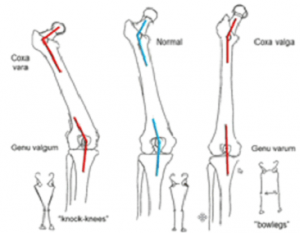

⦁ از آن جایی که این بدشکلی باعث ایجاد ضعف عملکردی در عضلات ابداکتور هیپ می شود گیت ترندلنبرگ جبران شده یا نشده را ایجاد می کند.

⦁ این اختلال سطح تماس فمور با استابولوم کاهش می یابددر نتیجه مفصل هیپ مستعد دررفتگی می شود.

۳)ترکیبی: در اختلالات نوروماسکولار مثل فلج مغزی، این بدشکلی معمولا ترکیبی از آنته ورژن فمور به همراه کوکسا والگا واقعی است.

۱)اختلالات نوروماسکولار مثل فلج مغزی

۲) معمولا همزمان با آنته ورژن فمور رخ می دهد.